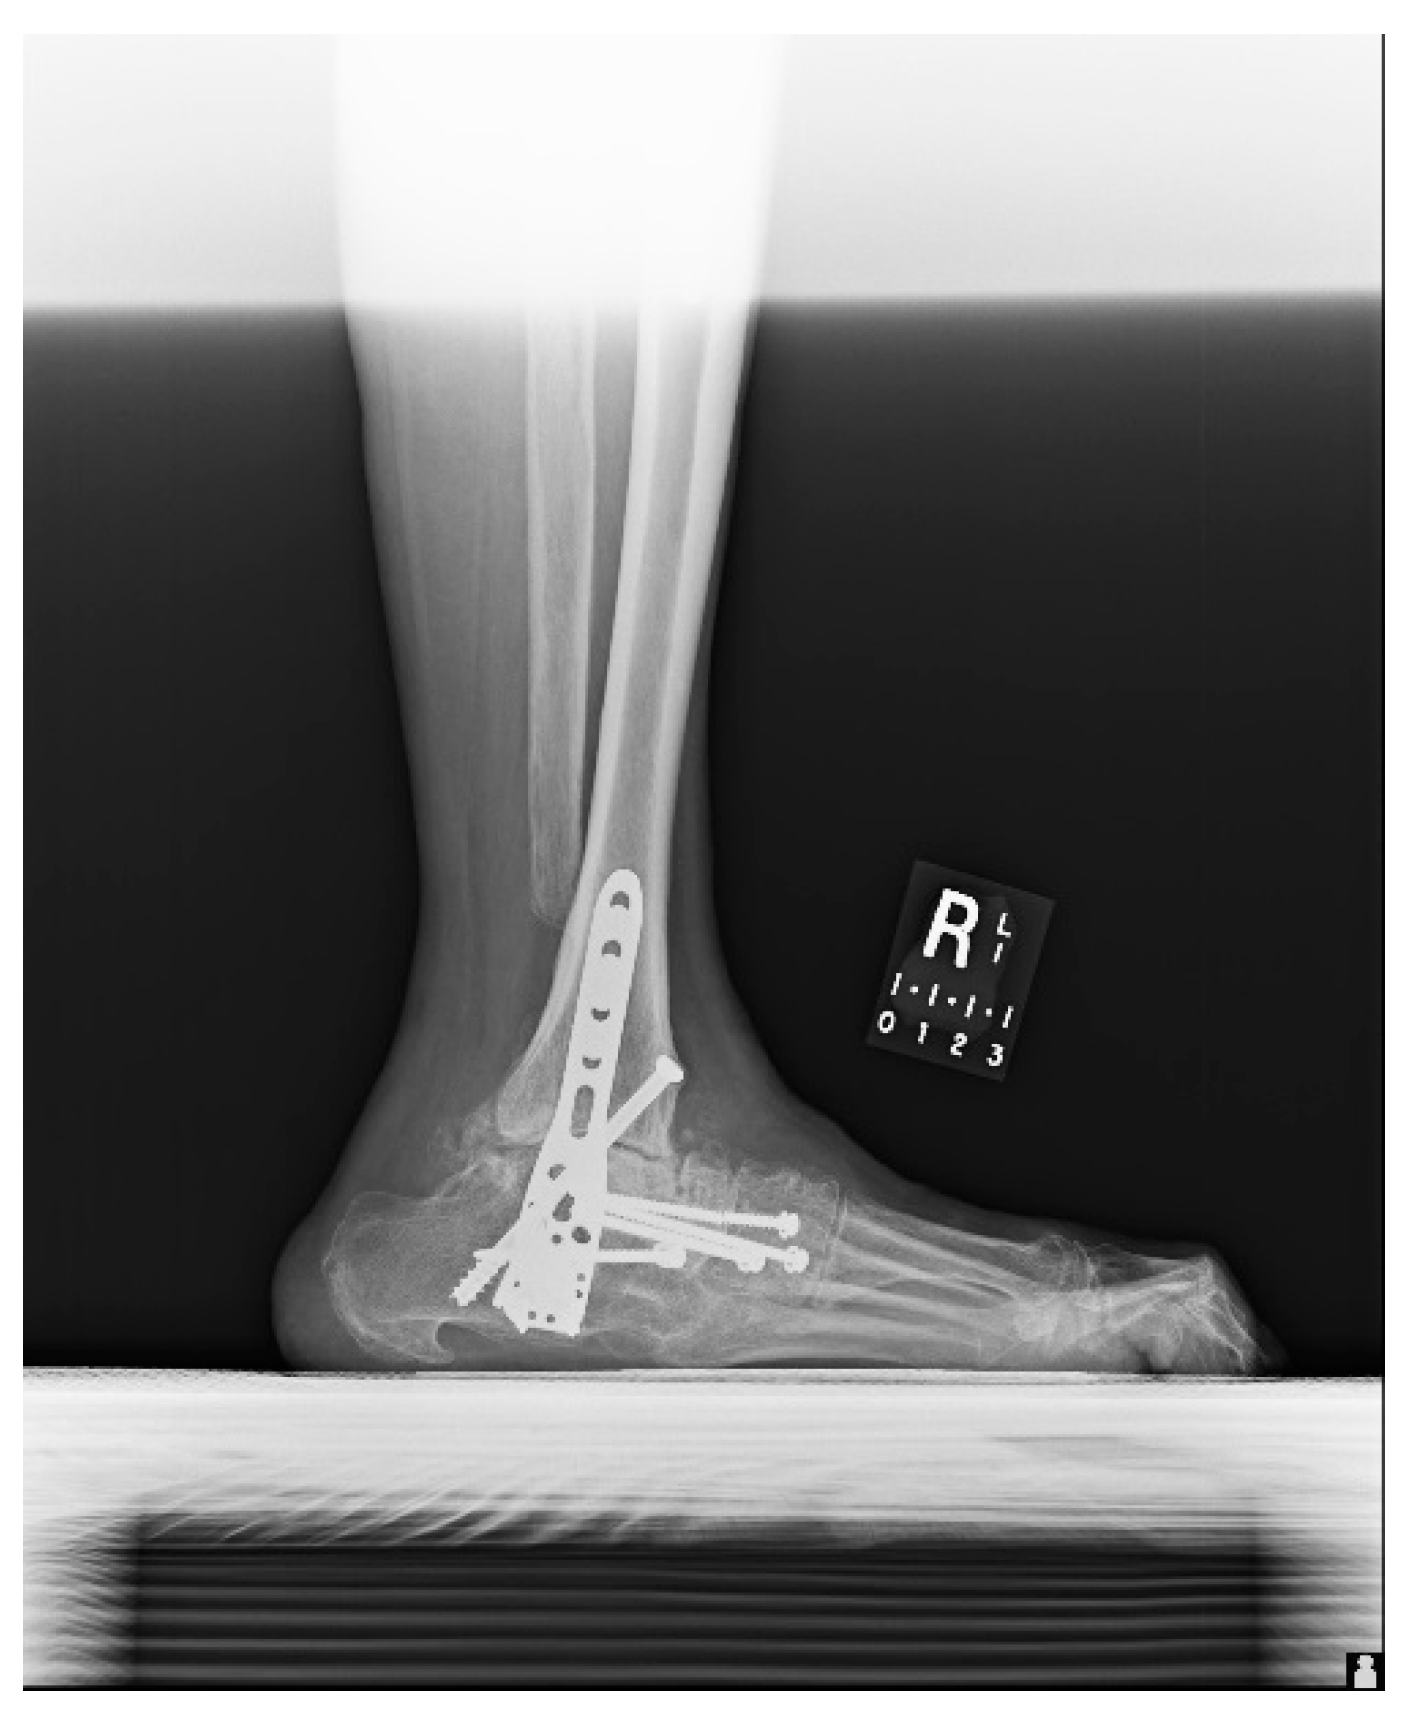

1.1. Case Presentation (Clinical Summary)

1.1.1. Initial Presentation

1.1.2. Operation

1.1.3. Post-Operative Follow-Up

1.1.4. Post-Operative Imaging